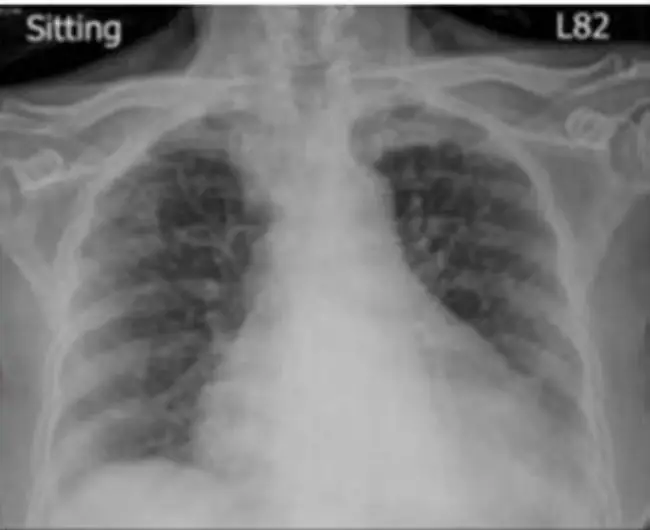

圖二(胸部 X 光,坐位,L82):

- 心臟輪廓明顯擴大(cardiomegaly),心胸比(cardiothoracic ratio)增加

- 雙肺可見血管紋路增粗,